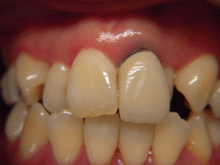

A G C

ガルバノテクニックを用いて作製されるセラミックであり、純金を用いる事によって生体親和性に優れ、歯肉にもやさしく、最適な適合精度と最適なマージン適合性が得られます。

症 例